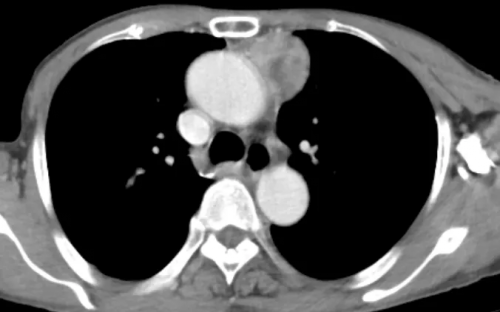

来自渔溪镇的万大爷,因此前无明显诱因出现胸闷、胸痛,且呼吸时疼痛加重,遂到恩阳区人民医院门诊就医。CT检查提示“纵膈占位”,随即收入胸外科(外一科)住院治疗。科主任陈旭在组织胸外科团队进行充分讨论分析后,拟行难度更大、创伤更小的“经剑突下入路胸腔镜纵膈肿瘤切除术”为患者治疗,并于近期成功实施该手术。 经剑突下入路胸腔镜纵膈肿瘤切除术相较于传统纵膈肿瘤切除术而言,具有术后伤口美观、疼痛减轻、暴露充分、标本易取出等优点。并且能彻底避免手术对肋间神经和肌肉等胸壁组织损伤,较好保持胸壁完整性,降低术后对呼吸功能的影响,缩短了胸管留置体内的时间和患者住院时间,有利于患者快速康复。